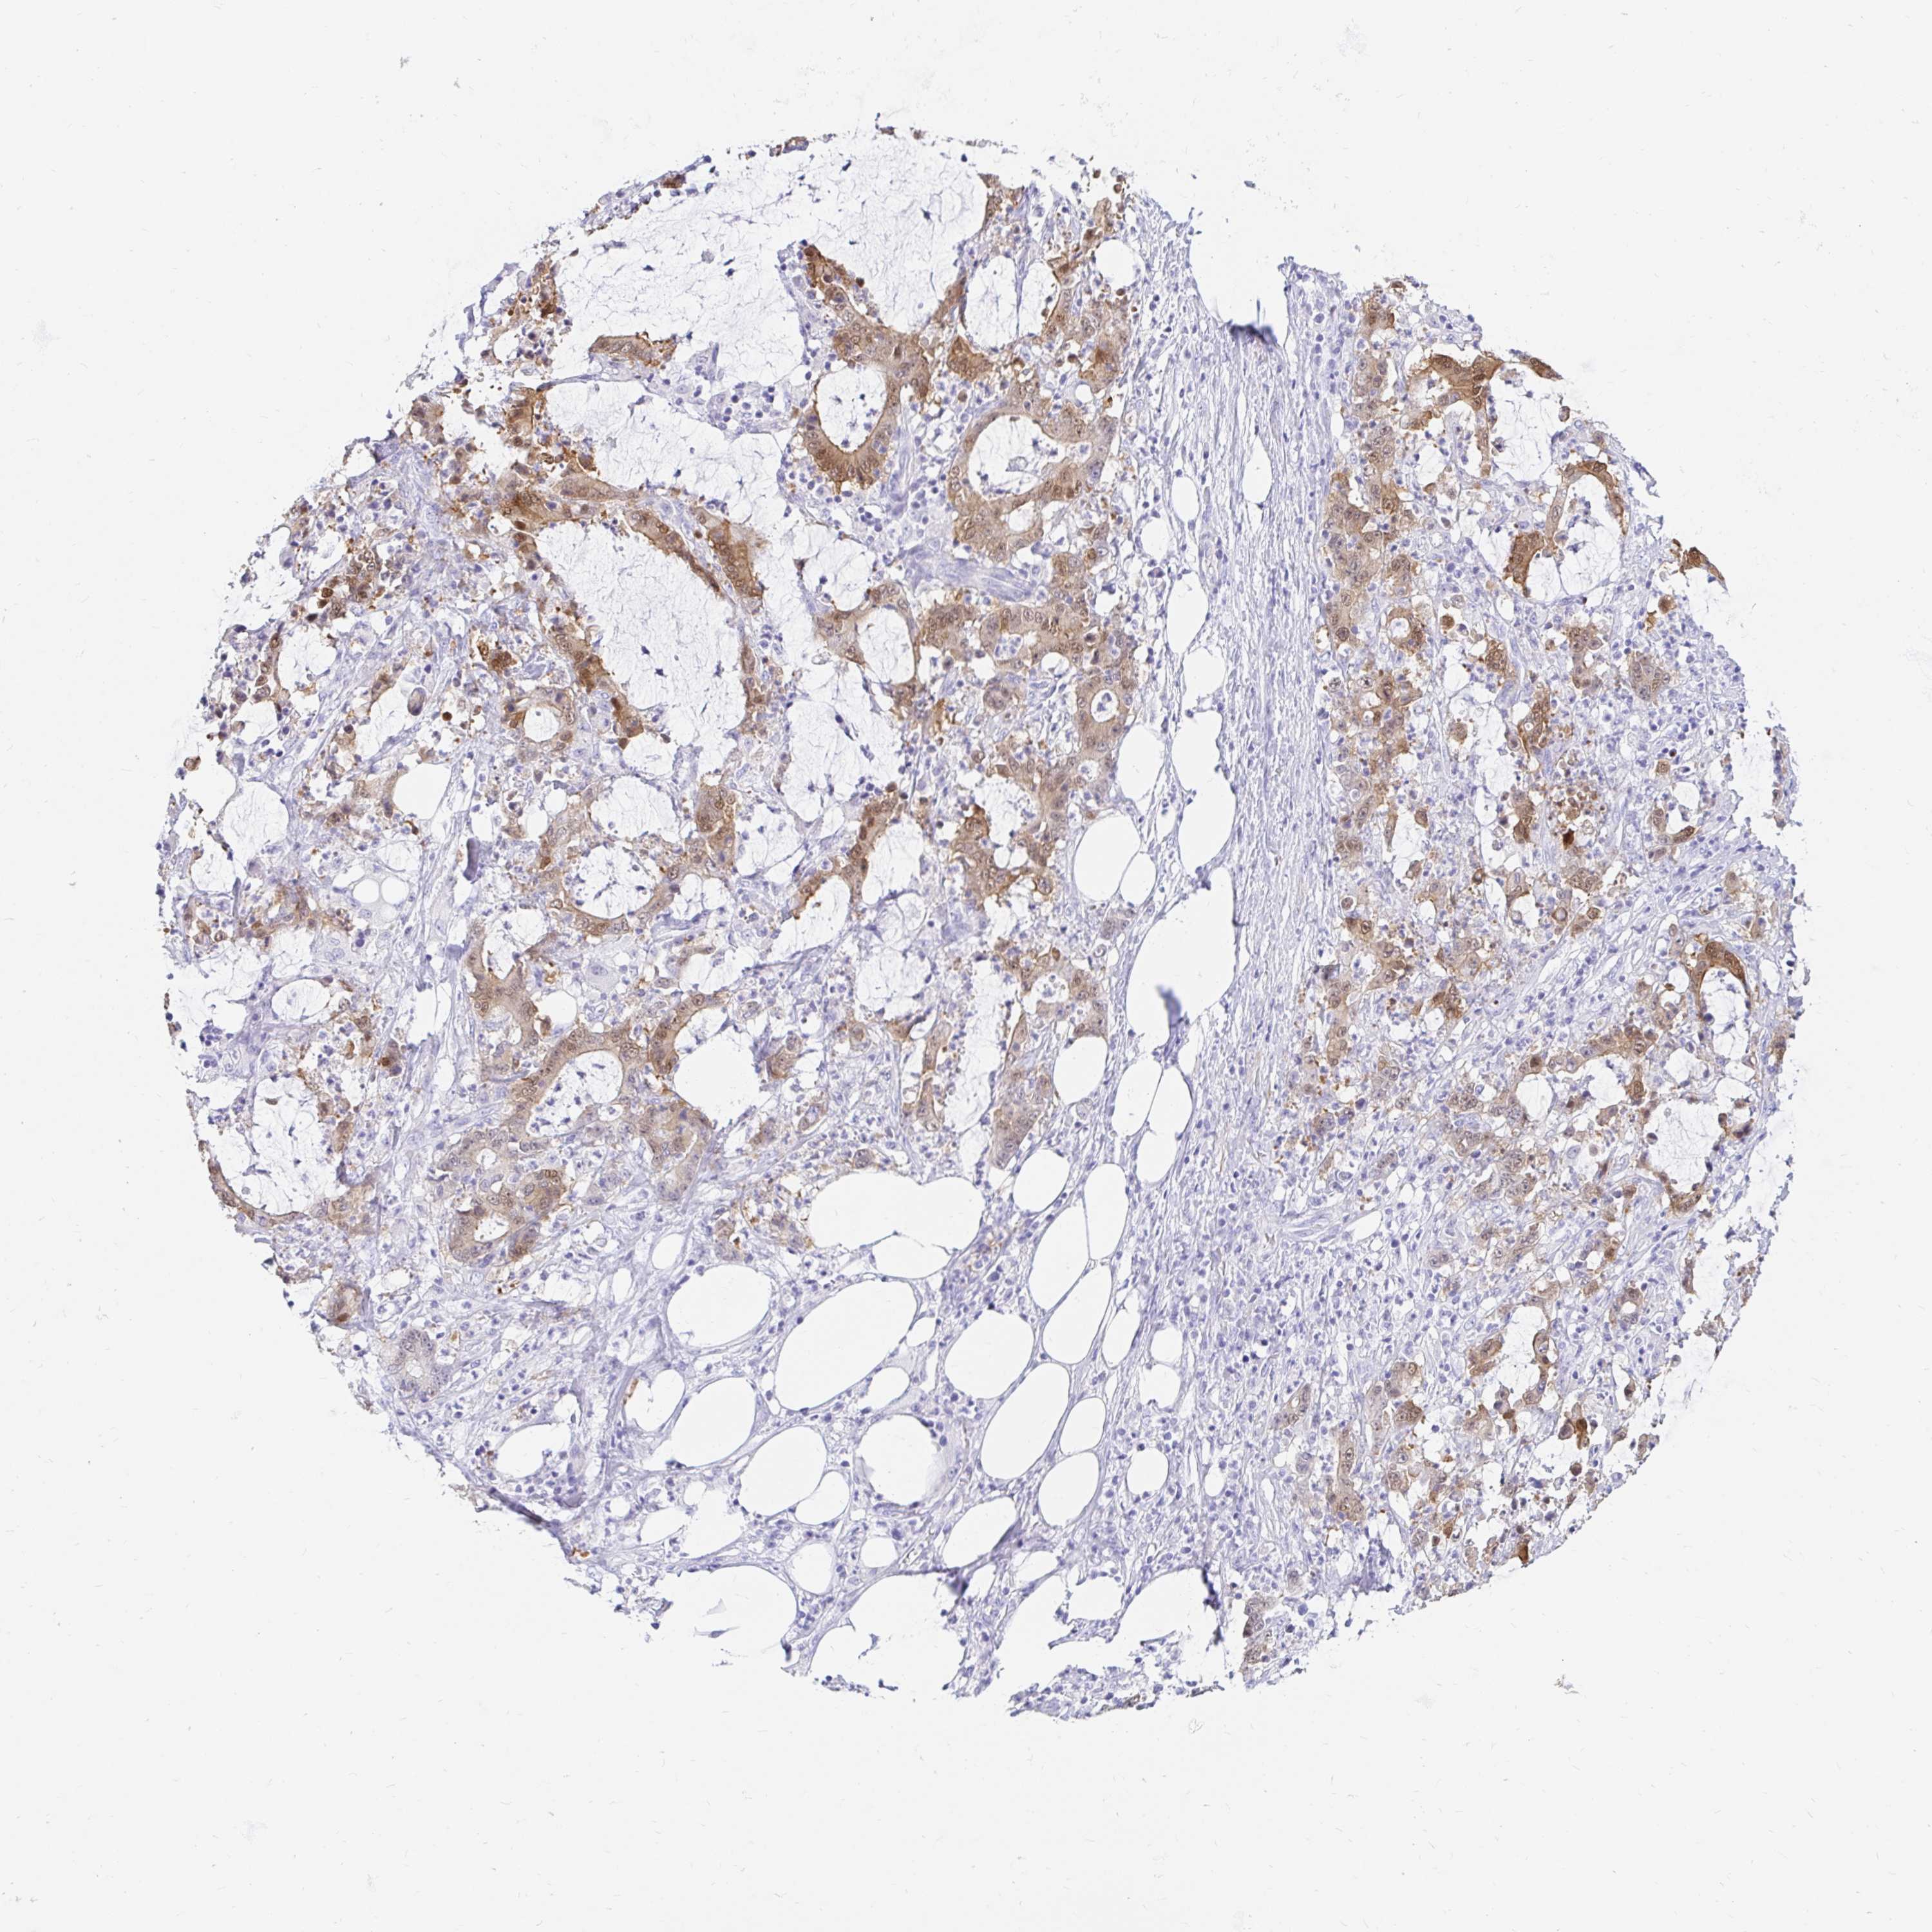

STOMACH CANCER - Protein expressioni

A mouse-over function shows sample information and annotation data. Click on an image to view it in a full screen mode. Samples can be filtered based on level of antibody staining by selecting one or several of the following categories: high, medium, low and not detected. The assay and annotation is described here.

Note that samples used for immunohistochemistry by the Human Protein Atlas do not correspond to samples in the TCGA dataset.

Antibody stainingi

Antibody staining in the annotated cell types in the current human tissue is reported as not detected, low, medium, or high, based on conventional immunohistochemistry profiling in selected tissues. This score is based on the combination of the staining intensity and fraction of stained cells.

Each image is clickable and will lead to virtual microscopy that enables deeper exploration of all samples and also displays staining intensity scores, fraction scores and subcellular localization as well as patient and tissue information for each sample.

Antibody HPA048630

Antibody HPA061142

Antibody CAB004026

Staining

High

Medium

Low

Not detected

Intensity

Strong

Moderate

Weak

Negative

Quantity

>75%

75%-25%

<25%

None

Location

Nuclear

Cytoplasmic/membranous

Cytoplasmic/membranous,nuclear

Adenocarcinoma, NOS

Adenocarcinoma, High grade